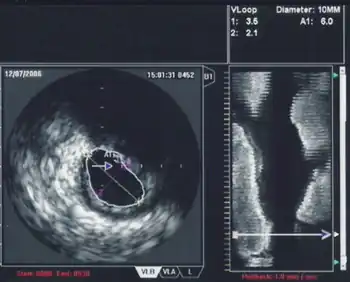

Intravascular ultrasound (IVUS) or intravascular echocardiography is a medical imaging methodology using a specially designed catheter with a miniaturized ultrasound probe attached to the distal end of the catheter. The proximal end of the catheter is attached to computerized ultrasound equipment. It allows the application of ultrasound technology, such as piezoelectric transducer or CMUT, to see from inside blood vessels out through the surrounding blood column, visualizing the endothelium (inner wall) of blood vessels.[1]

The ultrasound catheter tip is slid in over the guidewire and positioned, using angiography techniques so that the tip is at the farthest away position to be imaged. The sound waves are emitted from the catheter tip, are usually in the 20-40 MHz range, and the catheter also receives and conducts the return echo information out to the external computerized ultrasound equipment which constructs and displays a real time ultrasound image of a thin section of the blood vessel currently surrounding the catheter tip, usually displayed at 30 frames/second image.

The (a) blood vessel wall inner lining, (b) atheromatous disease within the wall and (c) connective tissues covering the outer surface of the blood vessel are echogenic, i.e. they return echoes making them visible on the ultrasound display.

By contrast, the blood itself and the healthy muscular tissue portion of the blood vessel wall is relatively echolucent, just black circular spaces, in the images.

Heavy calcium deposits in the blood vessel wall both heavily reflect sound, i.e. are very echogenic, but are also distinguishable by shadowing. Heavy calcification blocks sound transmission beyond and so, in the echo images, are seen as both very bright areas but with black shadows behind (from the vantage point of the catheter tip emitting the ultrasound waves).